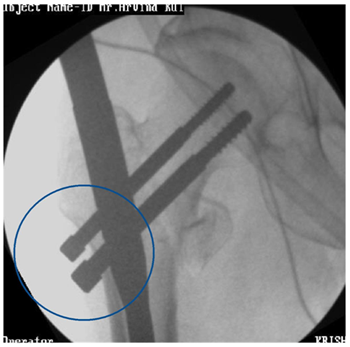

Indications (Figure 1)

1. Unstable IT fractures

1. Comminuted

2. Reverse oblique

3. Subtrochanteric extension

2. Associated shaft fracture

Figure 1 PFN in IT fractures.